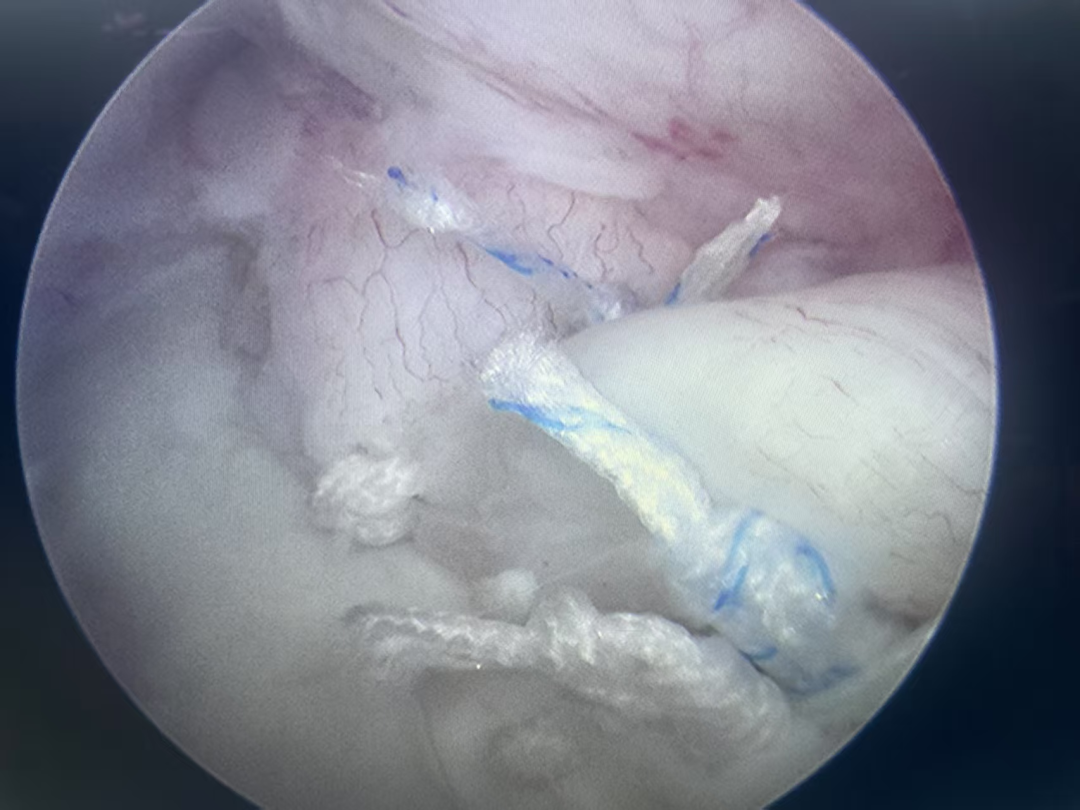

关节镜手术中,显示器上清晰可见的盂唇损伤画面。

在微创的肩关节镜下,一切都真相大白!镜头清晰地显示,孙先生的肩关节后上盂唇存在一处典型的撕裂,这正是他长期疼痛的根源。

“真凶”找到,接下来的治疗便水到渠成。罗学辉团队在关节镜下,用精巧的缝合技术,将撕裂的盂唇重新固定回原位,修复了关节的稳定性。手术非常成功,术后两三天,孙先生便康复良好,顺利出院。

镜下微创修复撕裂的盂唇。